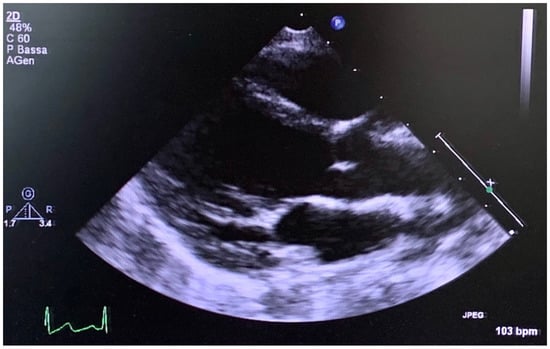

| Aortc root-z-score | 2.8 | 3.0 | 2.35 | N.R. | - | 5.0 before surgery |

| Ao | - | - | 31 normal size | Normal size | Normal size | Surgery at 38 years |